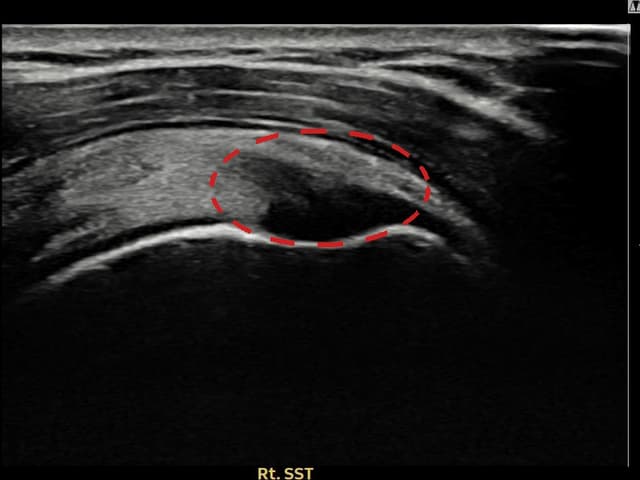

[経過期間: 23.07.31~23.09.27]

[縫縮術] 超音波検査にて左 棘上筋腱 부착부 광범위 部分断裂(13mm × 5mm (腱厚の約65%欠損))を確認。縫縮術施行後、腱の連続性が回復し、日常生活に復帰されました。